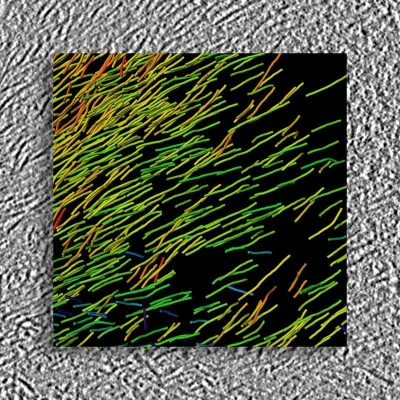

„Die einzelnen Aufnahmen in der Kryo-Elektronenmikroskopie sind meistens extrem verrauscht, weil Proteine sehr empfindlich gegenüber Elektronenstrahlung sind und die Bilder nur mit einer geringen Strahlungsintensität erzeugt werden können“, erklärt Jun.-Prof. Gunnar Schröder vom Forschungszentrum Jülich und der Heinrich-Heine-Universität Düsseldorf. Mithilfe eines computergestützten Verfahrens hatte er Tausende Einzelbilder kombiniert und so die hochaufgelösten Strukturdaten aus den Aufnahmen extrahiert.

„Das ist ein Schritt, der sehr kompliziert sein kann, wenn die Probe heterogen ist, also aus vielen unterschiedlich geformten Fibrillen besteht. Bei den Amyloid-Fibrillen war das bisher fast immer der Fall und stellte eines der wesentlichen Hindernisse für die Analyse dar. Aber nun hatten wir eine ziemlich einzigartige Probe mit sehr homogenen Fibrillen – 90 Prozent hatten die gleiche Länge und Symmetrie“, so Schröder.